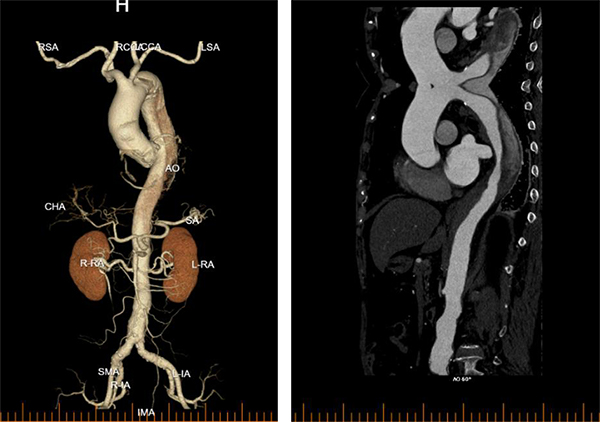

李阿姨今年79岁了,2026年2月27日一早起床,突然觉得胸背剧烈疼痛难忍,自己觉得可能心脏出问题了,家人赶紧拨打120送到东方医院急诊科。急诊科副主任张志辰接诊后依据丰富的临床经验初步考虑存在主动脉夹层可能,遂立即进行胸腹CT检查,并完成急查主动脉CTA,确诊患者为主动脉夹层B型!患者病情极为凶险,撕裂的主动脉如同一颗随时可能引爆的“炸弹”,时刻威胁着患者的生命。时间就是生命,必须立即启动急诊手术!

术中,周围血管科团队凭借丰富的临床经验和精湛的手术技艺,精准定位主动脉破口,成功植入覆膜支架,完整修复了撕裂的血管内膜,隔绝了假腔血流。术后造影显示支架位置良好,主动脉破口完全封闭,手术取得圆满成功。